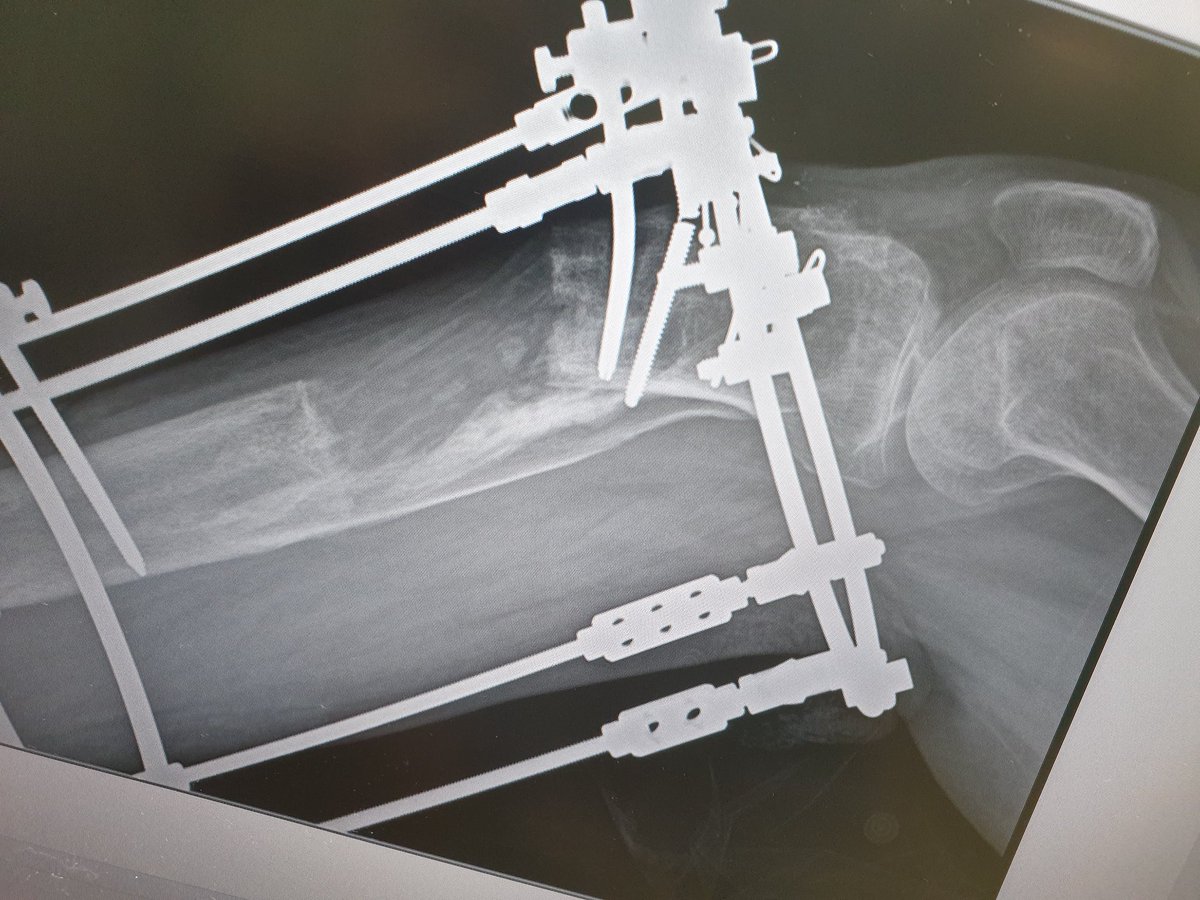

Case of septic non union distal tibia with reaction of infection and acute shortening and proximal lengthening osteotomy, pt develped procurvatum deformity due unstable ring , acute correction done of regenerate,notice the hinge position.